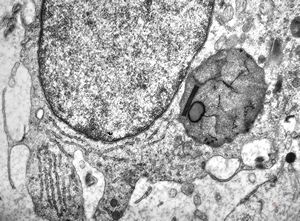

M,10y. | herpetic encephalitis